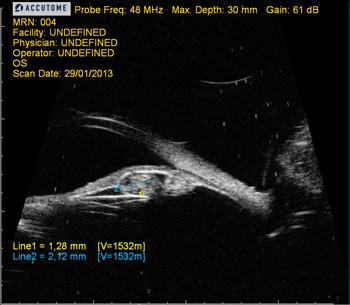

UBM (Biomicroscopia Ultrassonica) Accutome

Seu transdutor utiliza polímeros de fluoreto de polivinilideno (PVDF) como elemento piezoelétrico. As ondas sonoras emitidas em alta freqüência (48 MHz) aumentam a resolução das imagens, mas sofrem atenuação nos meios da propagação, reduzindo sua penetração, tornado o método ideal para o exame do segmento anterior do globo ocular, útil na avaliação da córnea, ângulo camerular, profundidade da câmara anterior e posterior, análise da iris e corpo ciliar, esclera e conjuntiva, bem como cristalino, medida de branco a branco para planejamento de lentes fácicas e avaliação de posicionamento de lentes intra-oculares.

O sistema UBM plus (Accutome) ainda proporciona alta resolução e avaliação com modo A.